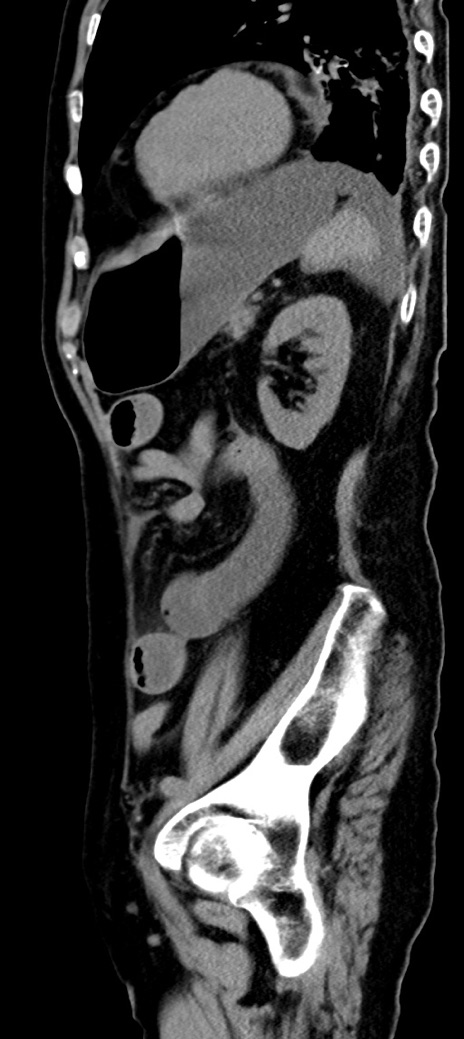

症例40(矢状断像)他院1日前

【症例】90歳代女性

【主訴】腹痛・嘔吐

【現病歴】 食欲低下、嘔吐があり昨日他院受診。肺炎と診断され入院となる。入院後より腹部全体に圧痛あり。胃管留置され経過みていたが、症状持続するため、

当院転院となる。

【既往歴】胸椎圧迫骨折、胆石症

【身体所見】腹部:中央に激痛あり、圧痛あり、反跳痛不明

【データ】WBC 17100、CRP 18.82